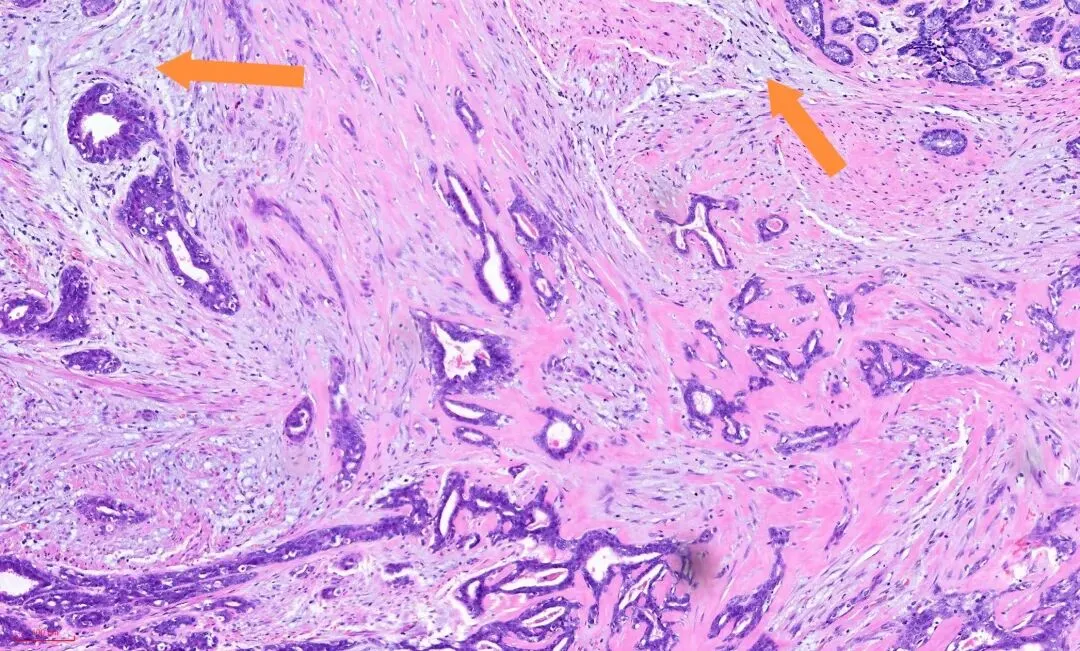

在视野中心看到粉染的硬化的纤维结缔组织,其内有受挤压变形的腺体,其周边有增生的腺体,如下图:

那么下图的结构又怎么理解呢?是浸润性癌吗?

左下角的这些腺上皮与右上角正常的腺上皮细胞是一样的,而左下角腺上皮周围的粉染的条索样的成分与右上角正常小叶的肌上皮成分是一样的,也就是说这部分应该是增生的腺上皮和肌上皮。免疫组化也证实了这一点。

所以,即便是这样的杂乱无章,貌似癌的浸润,也还是良性的,这时应仔细观察细胞的异型性。如果是癌,细胞异型性是很大的,如下图:癌性的间质促纤维反应,也是粉染的,但不像硬化性腺病那样去挤压腺体,而是腺体与间质之间有一些裂隙,更大的区别在于细胞异型性,常有丰富的嗜酸性胞质,有不同的核级,核从规则到多形性,核大深染,核仁明显,核分裂象易见。如下图: